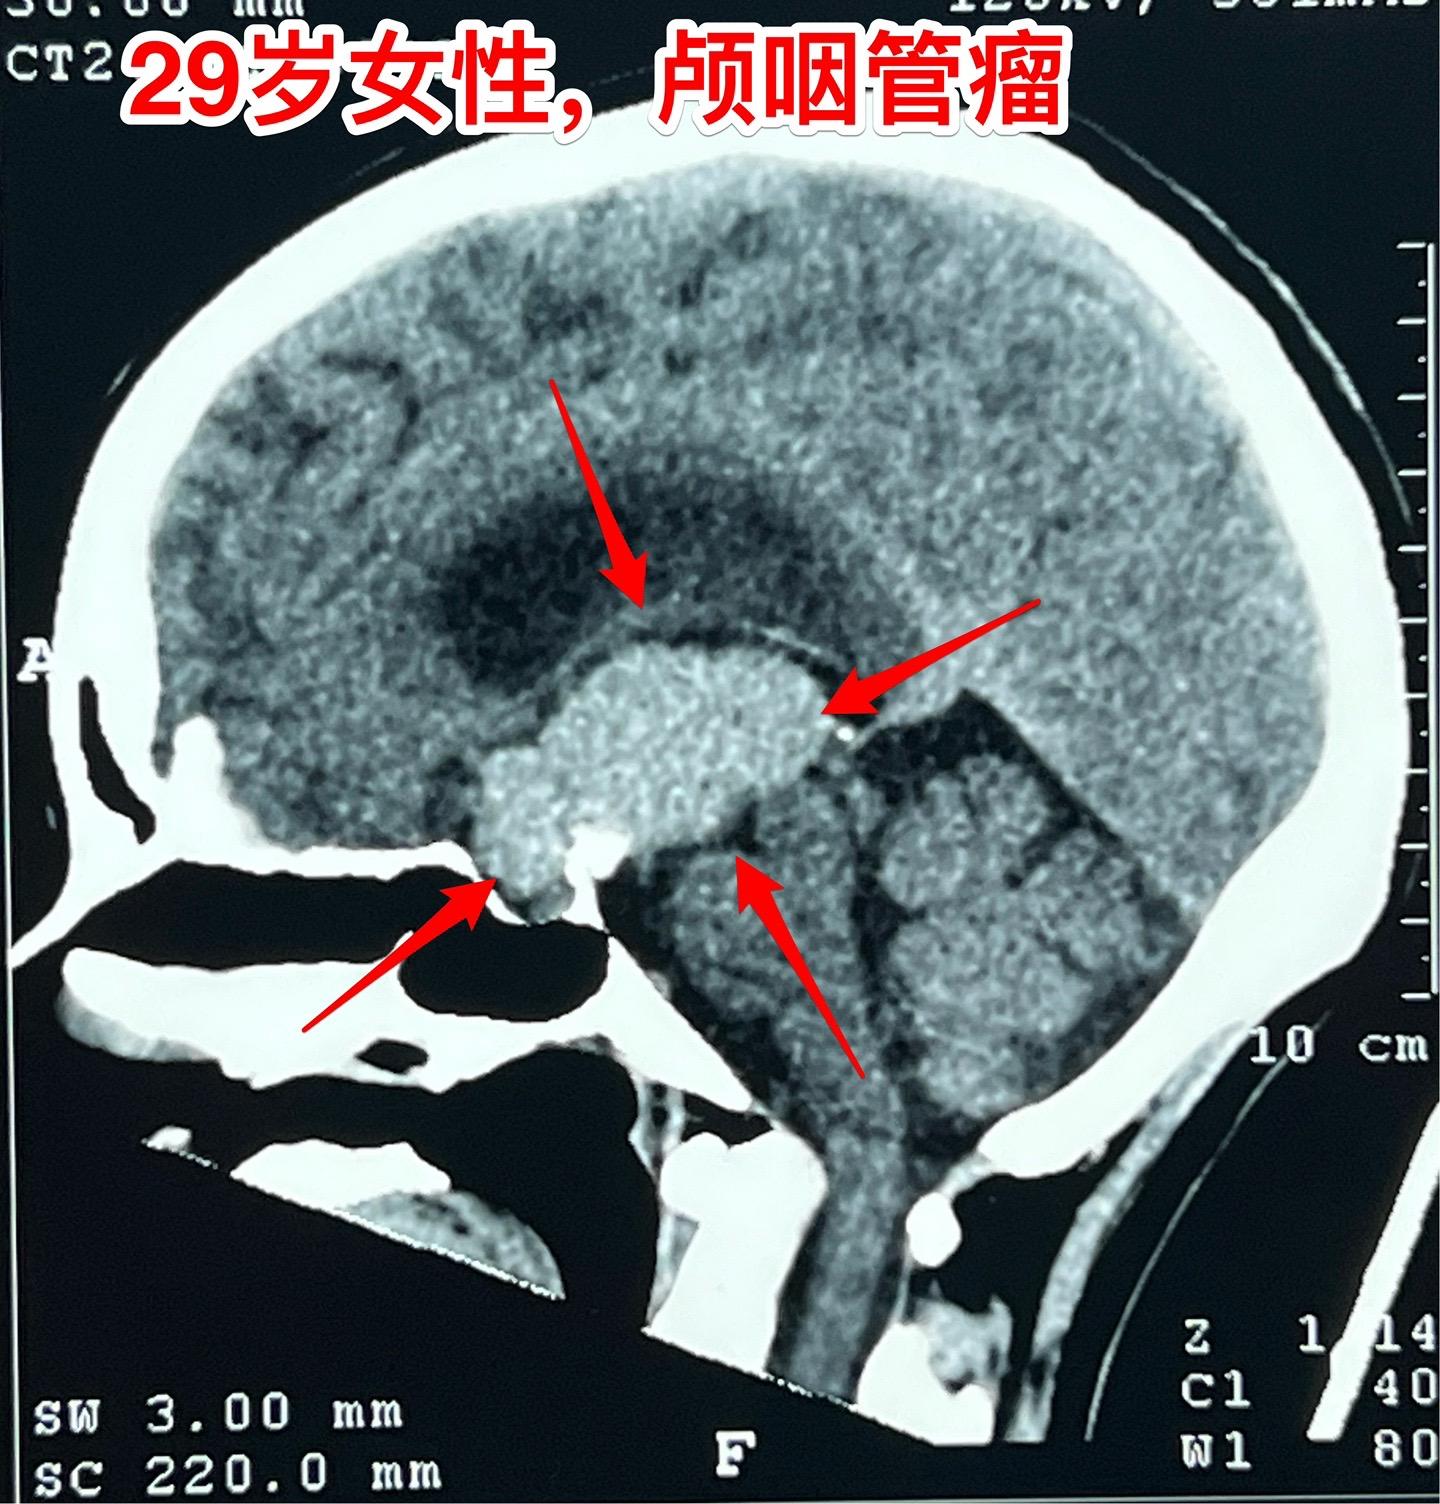

大理市女教师患颅咽管瘤。29岁大理市女老师,因头晕,内分泌功能障碍到医院行脑部CT及磁共振检查,发现颅咽管瘤。CT显示肿瘤有钙化,是典型的造釉细胞性颅咽管瘤。 患者家人系医务工作者。发现颅咽管瘤后即来北京就医。到我院检查视力视野,有视野缺损。 今日在我科作了颅咽管瘤切除手术,手术后5小时病人即清醒了。肿瘤完全切除,垂体柄结构完整,漏斗保留约三分之一。